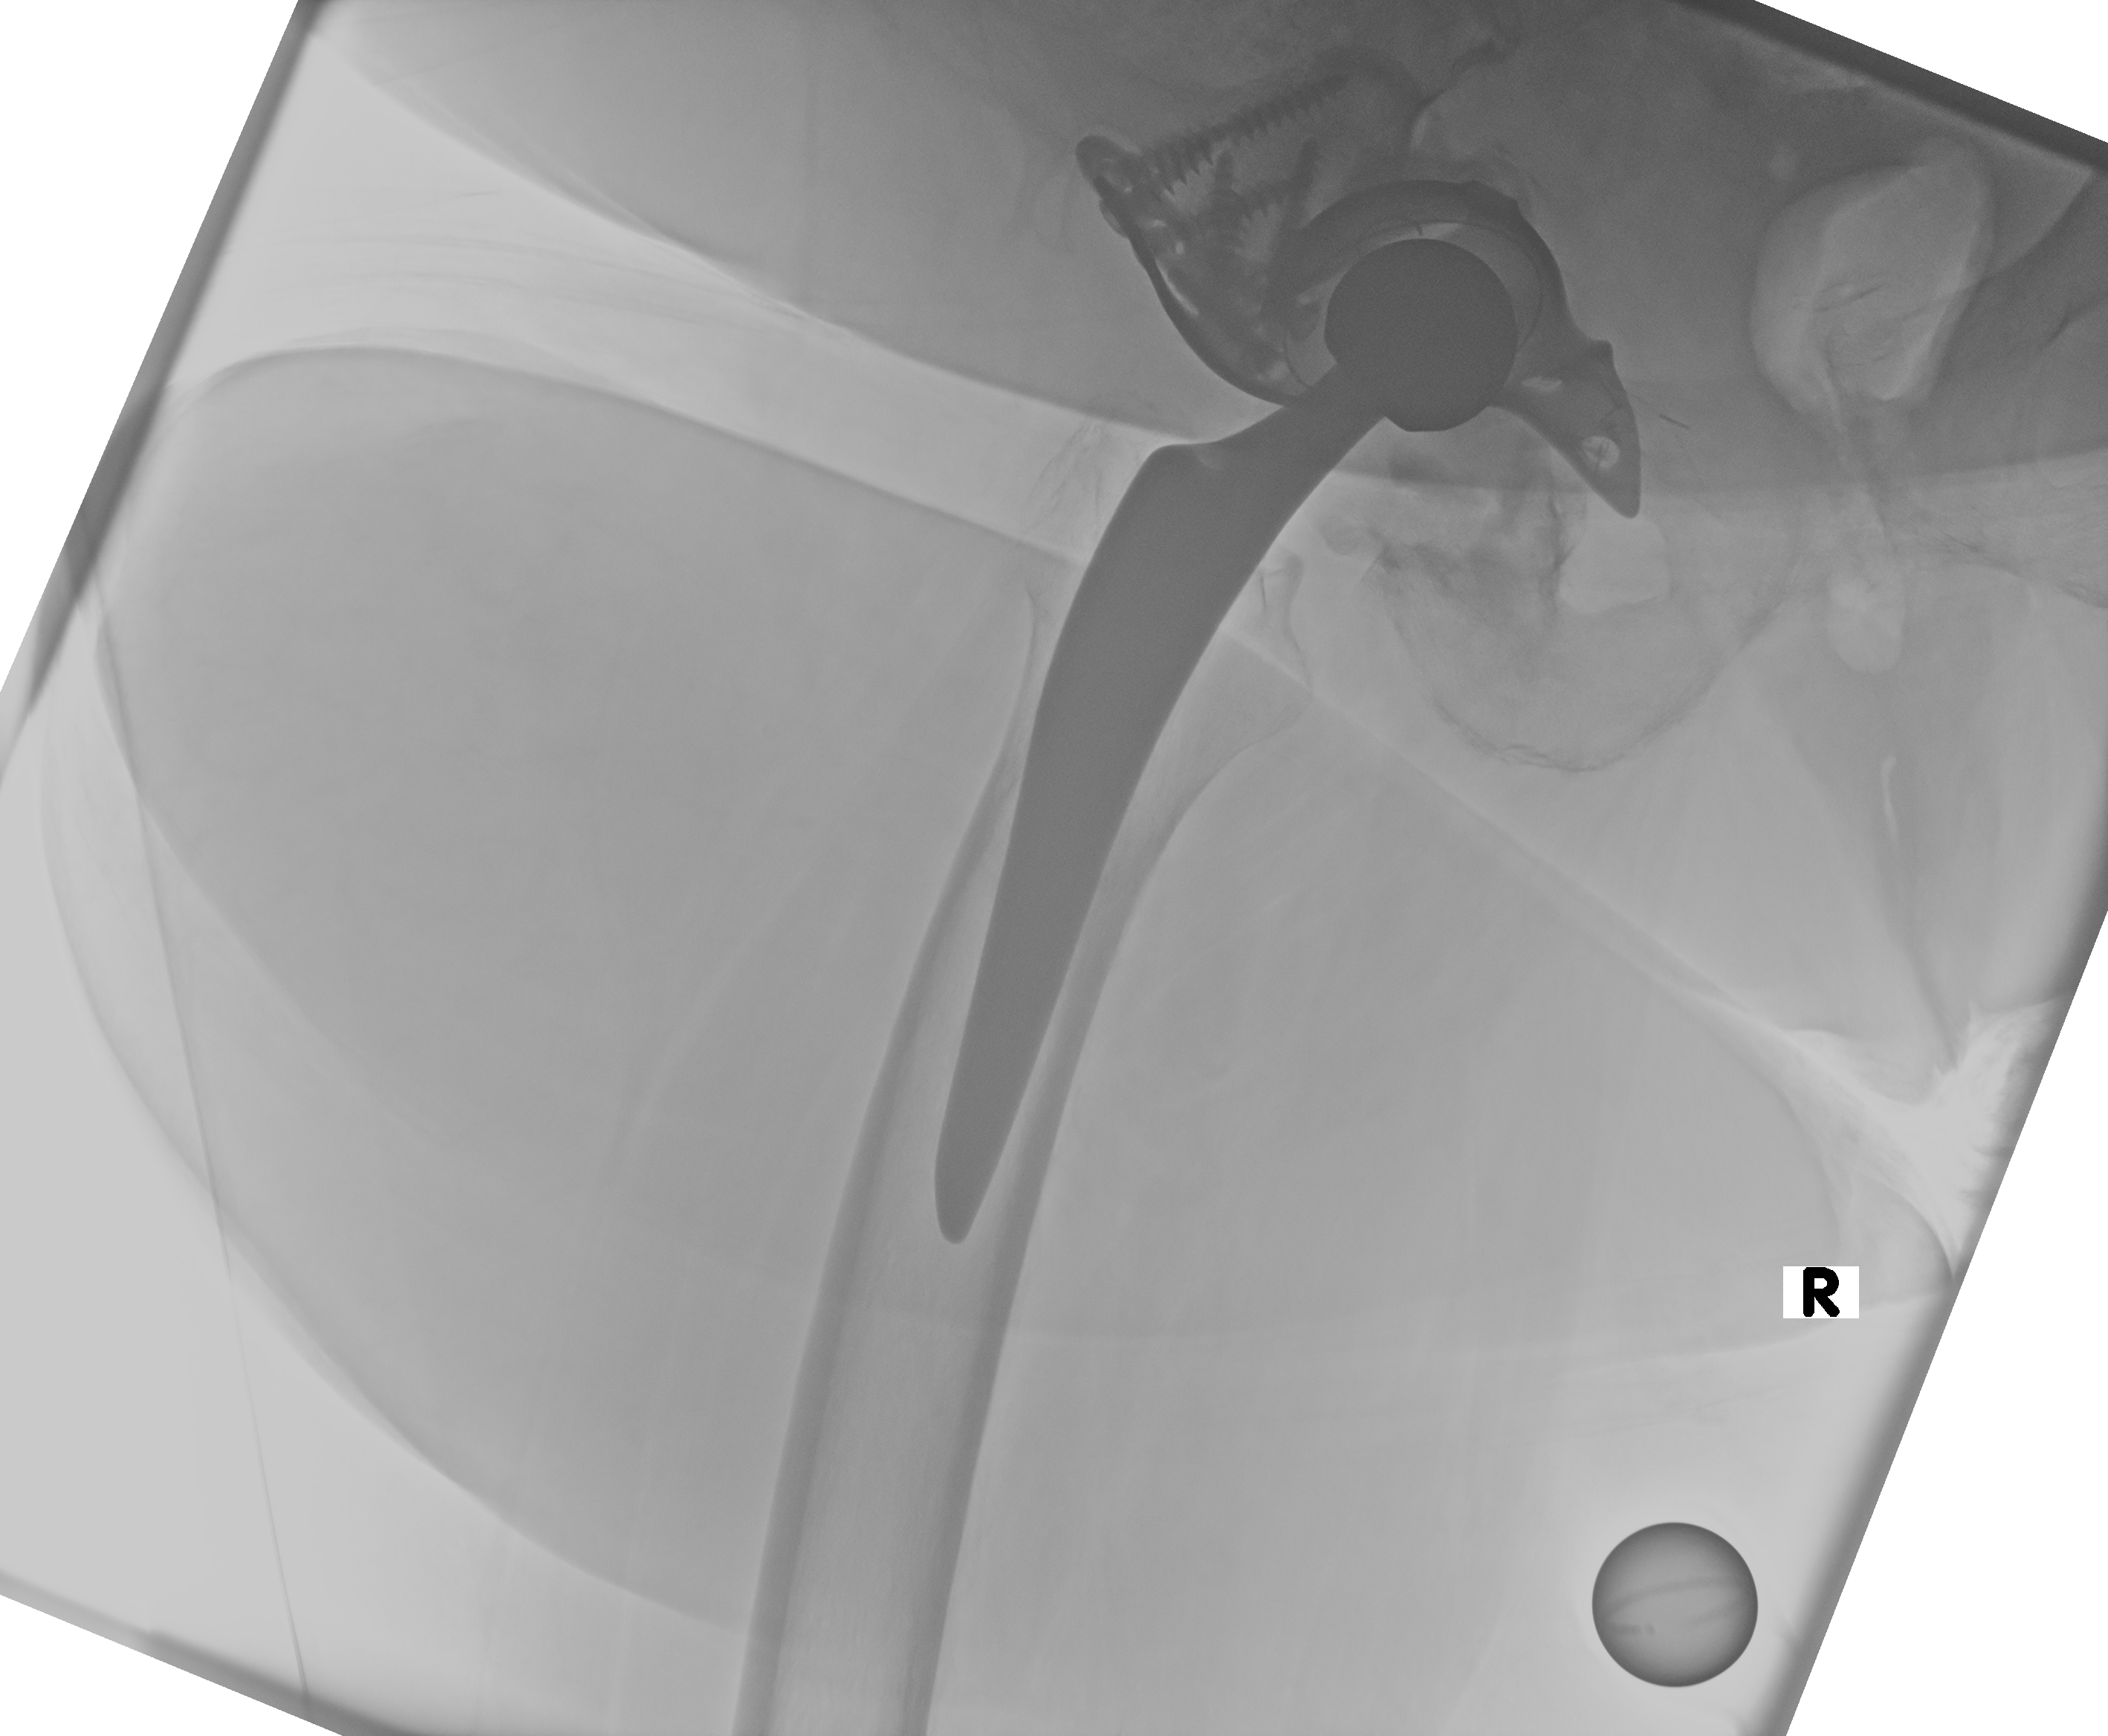

12.02.2026

Röntgen Becken + Hüfte rechts (Präoperativ, mit Spacer)

2 Aufnahmen | Becken tief mit King Mark + Hüfte Lauenstein R

12. Februar 2026

Präoperatives Röntgen

Röntgen Becken tief mit King Mark + Hüfte Lauenstein R. Aufnahmen mit Spacer vor Wiedereinbau.

12.02.2026 - PRÄOP

Röntgen Becken tief mit King Mark

DICOM

Präoperativ mit Spacer vor Wiedereinbau

Röntgen Hüfte Lauenstein R